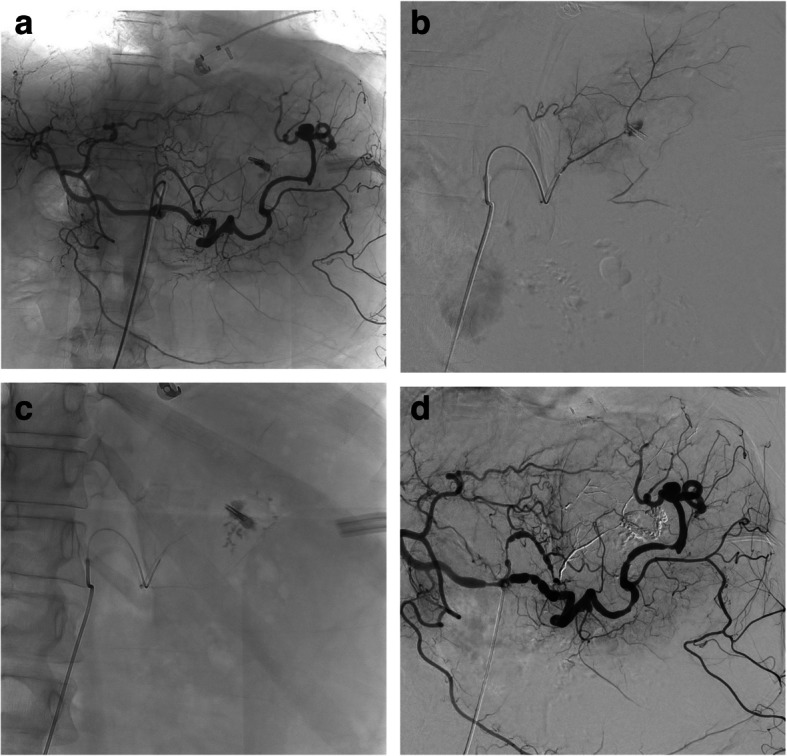

Purpose: Our purpose was to assess the feasibility and the short-term safety and efficacy outcomes of a wide range of transcatheter arterial and venous embolisation procedures done using α-hexyl-cyanoacrylate (AHCA)-MagicGlue® in patients with bleeding and non-bleeding disorders.

Methods: This single-centre retrospective study included consecutive patients who underwent emergent or planned AHCA-MagicGlue® transcatheter embolisation between February 2019 and September 2023. Technical success, clinical success, 30-day mortality, and complication rates were evaluated.

Results: We included 101 patients with a mean age of 49.9 ± 20.5 years who underwent arterial (n = 43, 42.6%) or venous (n = 58, 57.4%) embolisation for bleeding (n = 16, 15.8%) or other reasons (n = 85, 84.2%). The technical success rate was 100%. After a mean follow-up of 2.2 months, the clinical success rate was 94% in patients with bleeding and 95% in other patients; 1 patient died of multi-organ failure unrelated to the procedure. In the 22 patients with prostatic artery embolisation, statistically significant improvements were recorded at 3 months versus baseline for the International Prostate Symptoms Score (IPSS) (10.0 ± 5.8 vs. 20.8 ± 7.3, p = 0.001), IPSS quality-of-life score (2.0 ± 1.4 vs. 5.0 ± 1.0; p = 0.001), and prostate volume (67.8 ± 38.0 mL vs. 96.7 ± 47.4 mL, p = 0.001). Adverse events occurred in 11 (10.9%) patients and were major in 4 and minor in 7 patients.

Conclusions: MagicGlue® transcatheter arterial and venous embolisation is feasible, effective, and safe for bleeding and non-bleeding conditions across a broad range of anatomic sites.